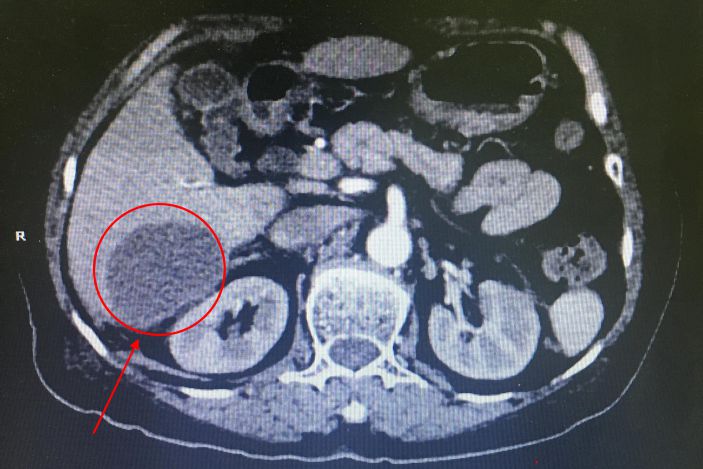

△術前病竈部位

經CT檢查發現患者肝右葉S5、S6、S7段多發膿腫,病竈最大的達6.0*4.2cm,結腸肝曲周圍炎性滲出。據了解,肝膿腫是肝髒化膿性病變,若不積極治療,死亡率達10%-30%。